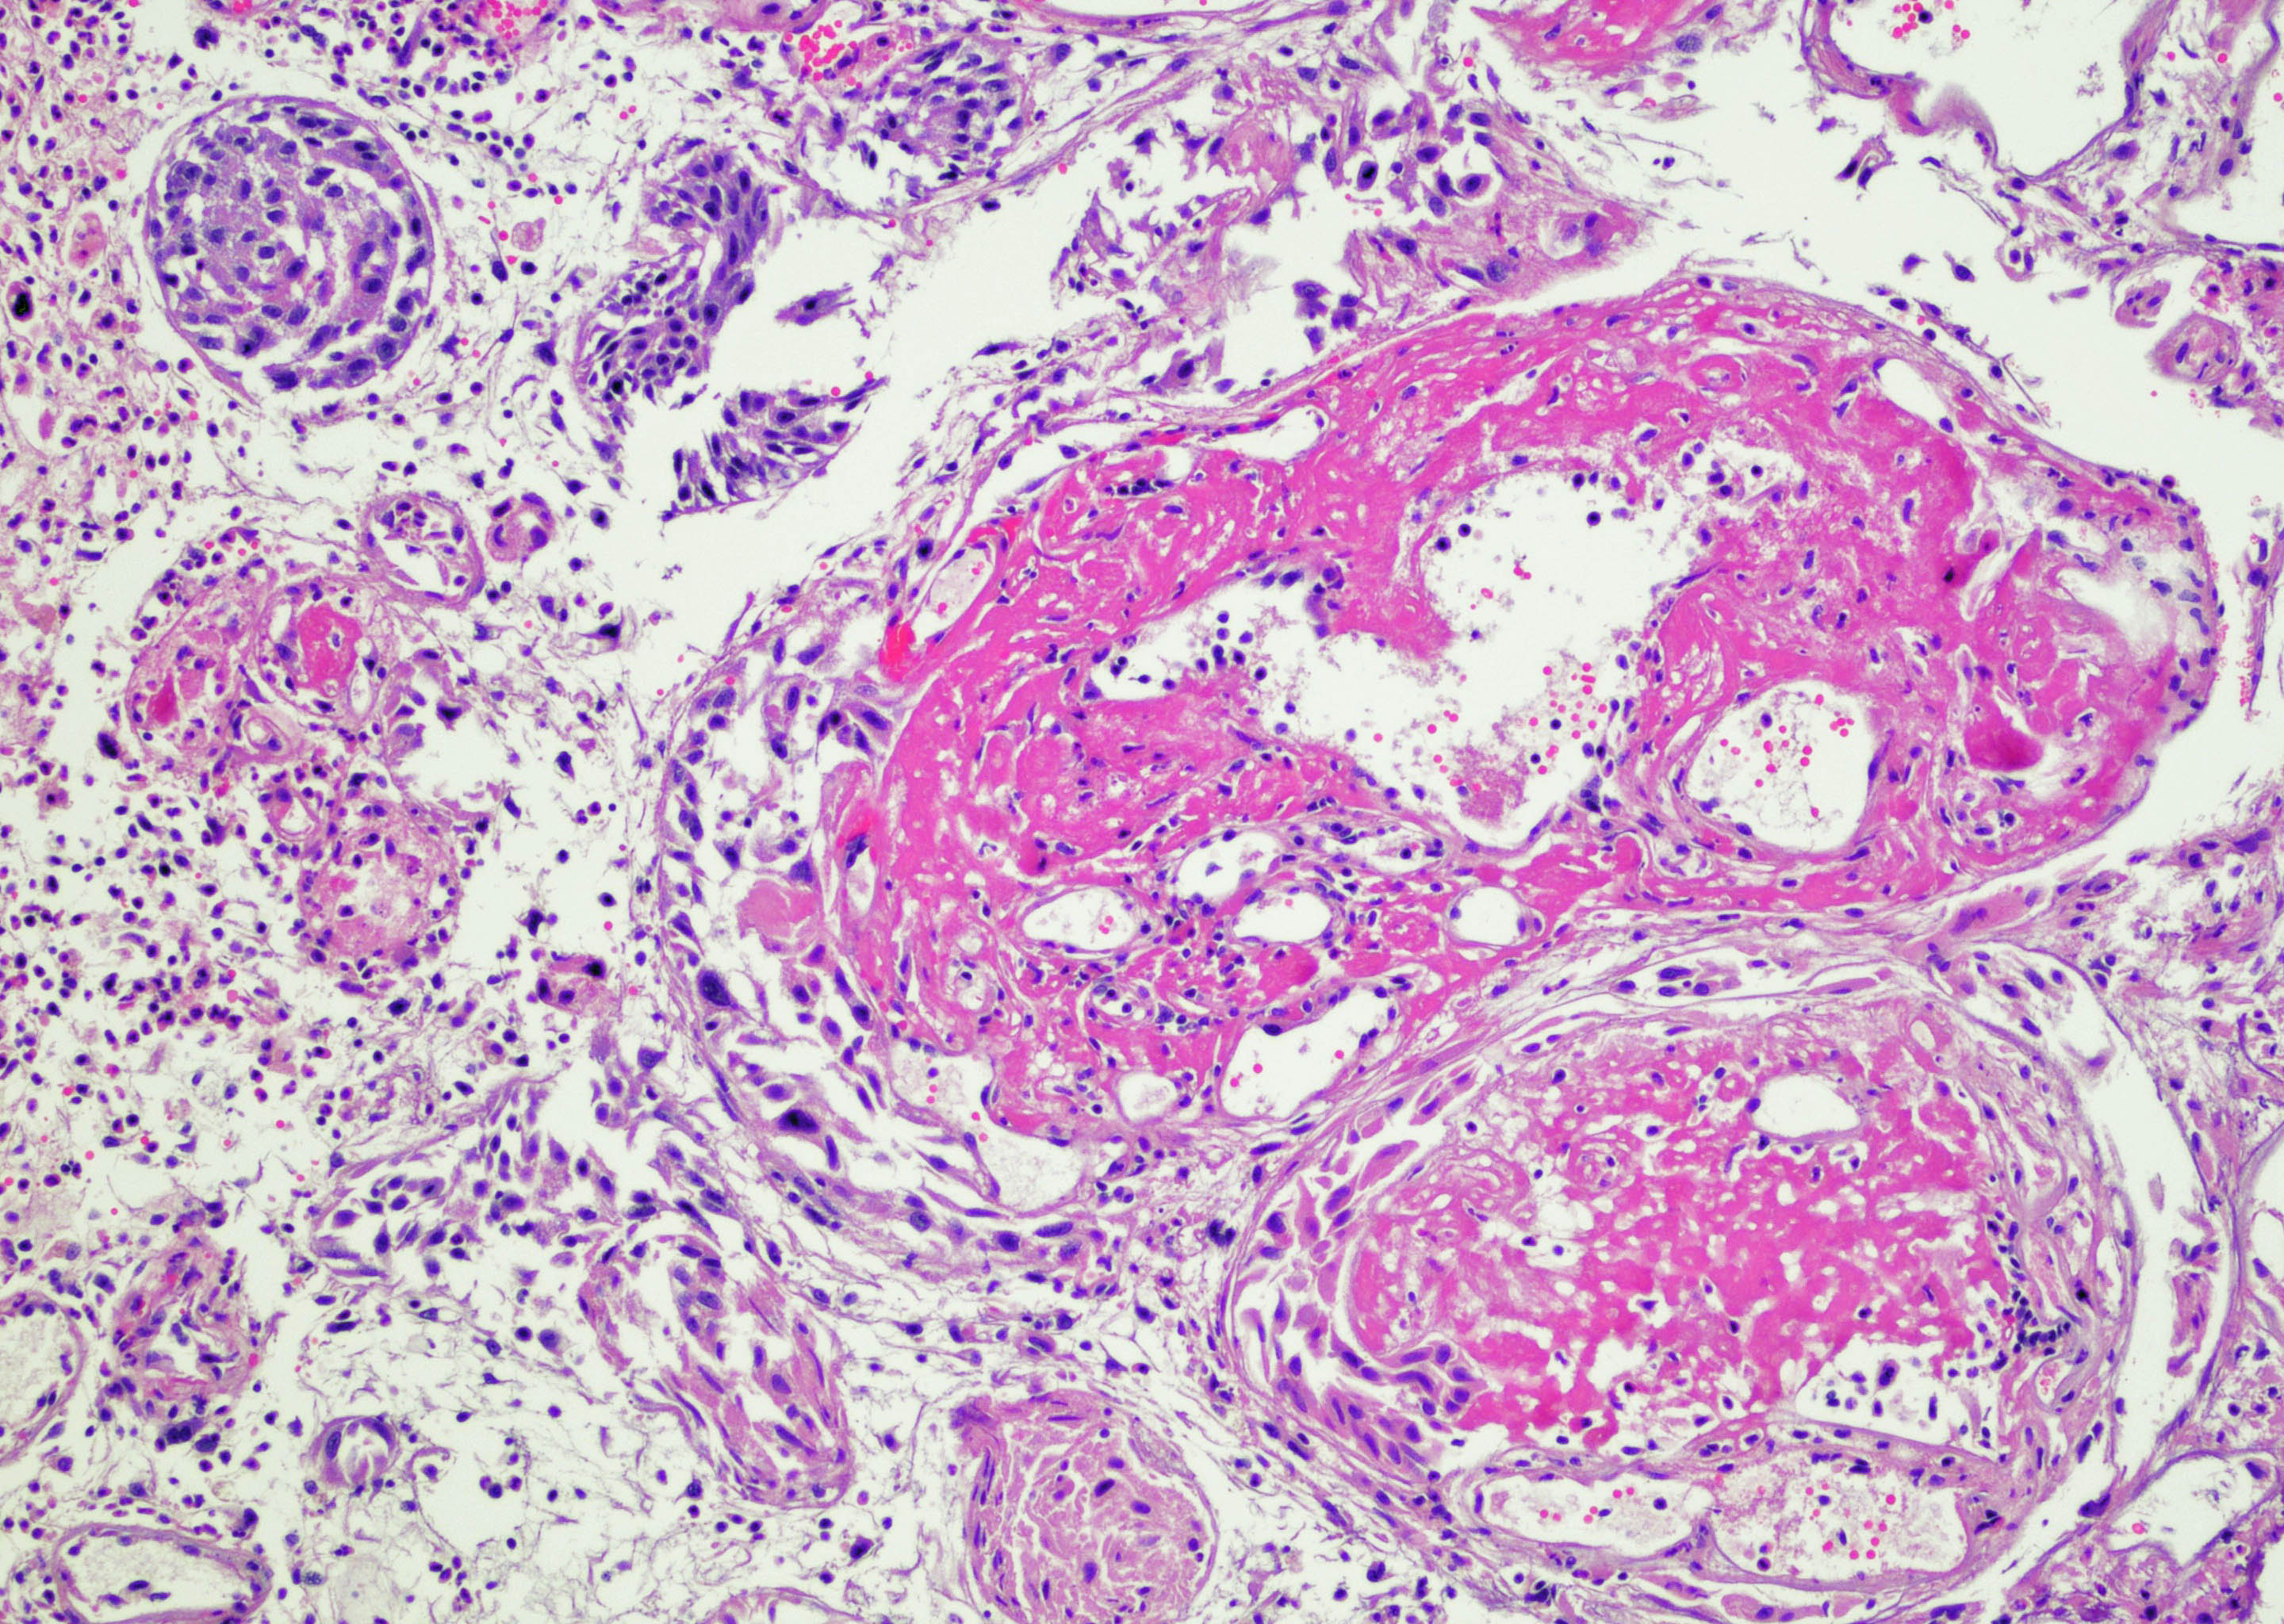

- Vessels with fibrin thrombi, fibrinoid vascular necrosis, vascular congestion, thickened walls, endothelial proliferation and telangiectasia

- Acute and chronic inflammation

- Reactive multinucleated stromal fibroblasts with smudgy nuclei

- Fibrosis and edema

- Hemorrhage and hemosiderin

- Pseudocarcinomatous urothelial hyperplasia: variable sized urothelial cords and nests with rounded or irregular edges present in the lamina propria and enclose dilated blood vessels with fibrin deposition (Am J Surg Pathol 2008;32:92)

- Acute phase: edematous, congested and telangiectatic vessels, acute and chronic inflammatory infiltrate, atypical stromal cells with multinucleated forms

- Chronic phase: atrophic urothelium, atrophic smooth muscle layer, collagen deposition (fibrosis) (Am J Surg Pathol 2004;28:909)

Microscopic (histologic) images

Contributed by Y. Albert Yeh, M.D., Ph.D. and Jennifer Lee, M.D.

- Comment: There is a history of radiation therapy per the medical record. The transurethral resection of the bladder lesion shows fragments of urothelial mucosa with total and partial denudation of urothelium. The urothelial lining cells show reactive changes. There is marked edema, hemorrhage and mixed inflammatory infiltrate composed predominantly of neutrophils and lymphocytes in the lamina propria. Reactive multinucleated stromal fibroblasts are seen. Telangiectatic vessels with fibrinoid necrosis and intravascular fibrin deposition are seen. Anastomosing cords and nests of urothelial cells encircling the vessels with fibrin deposition is evident. Urothelial cells with hyperchromatic nuclei, increased nuclear to cytoplasmic ratio and prominent nucleoli are seen. These features are consistent with radiation cystitis with pseudocarcinomatous urothelial hyperplasia. Muscularis propria is not identified in this specimen.

A 68 year old man presented with hematuria and dysuria. He has a medical history of prostate cancer that was treated with radiation therapy. Cystoscopy revealed hemorrhage in the right bladder wall. A transurethral resection of the lesion was performed. A photomicrograph is shown above. What is the diagnosis?

- Radiation cystitis with pseudocarcinomatous hyperplasia

C. Radiation cystitis with pseudocarcinomatous hyperplasia. Answers A, B and D are incorrect because anastomosing cords and nests of urothelial cells encircling ectatic vessels with intravascular and stromal fibrin deposition in a background of mixed inflammation are not present in these entities.